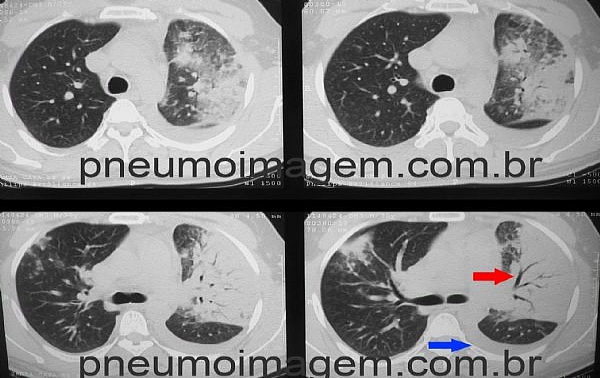

Veja imagens de pneumonia no PneumoImagem

clicando aqui.